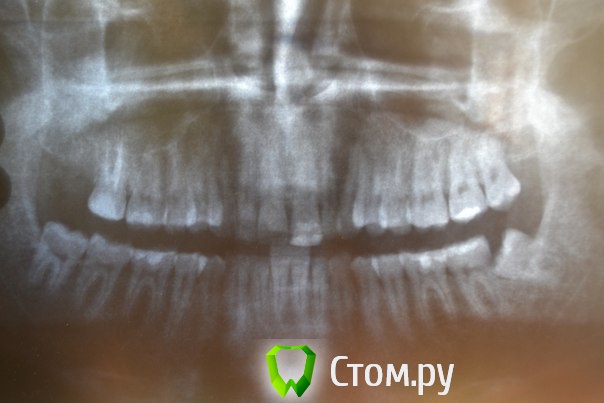

Доброго времени суток,помогите пожалуйстабеспокоит заложенность носа уже 3ий год,обший ослабленный иммунитет что выражается в частых простудах,возраст 25 лет,причина этого гдето в зубах,так как кроме этого проблем небыло никогда,когда начились эти проблему начал ходить к стомалогам мне сделали порядка 7 пломб,в одном был пульпит,как пульпит переличили стало легче но не до конца ,затем на мскт увидели кисту под депульпированной 7кой,

вот зуб пролечил у ильи мера,в 2 этапа,первый раз он сделал,и залили лекарство и сказал зуб врядли сохраним,через месяц второй прием все доделал и сказал что все хорошо,после этого общее состояние стало хуже,возможно из-за того что врач сказал что все с пульпы сливалось прямо в пазуху, вот это делали в марте ,после этого сделал мскт киста с зуба увеличилась с 1см до 1,5см, я лег в больничку местную и мнее ее вырезали,после этого прошел 1 месяц улучшений нет все также заложенность в носе и пониженный иммунитет,не подскажите что делать?кисту просто вырезали резекцую корня зуба не делали вот снимки до вырезания кисты после первого раза лечения каналов